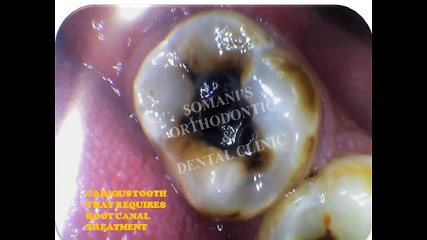

Root canal treatment (endodontics) is a dental procedure used to treat infection at the centre of a tooth.